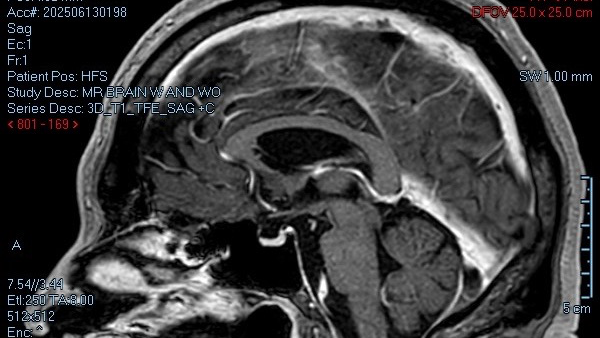

Hi. My name is Scott McDaniel. I was diagnosed with MS (multiple sclerosis) in July of 2025 after becoming ill in November of 2023. As of December 2025, my doctors are now leaning toward additional central nervous system, immune system and neurological diseases along with discovery in my MRIs of at least 2 strokes during my illness.

- My biggest fear right now is that the advanced hypertension and other medical issues are going to cause another stroke and I will not be able to communicate or move. The idea of being trapped in my own mind terrifies me beyond comprehension.